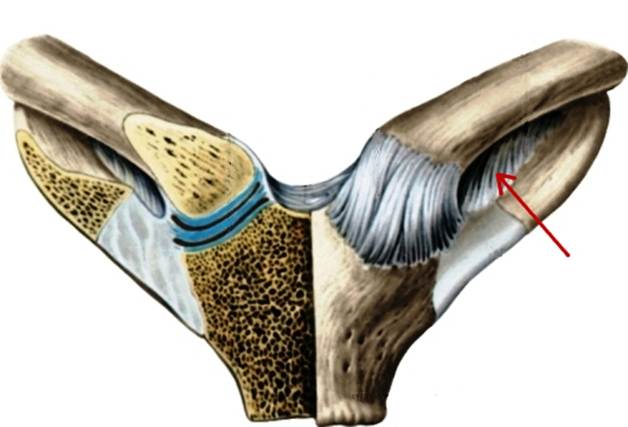

S: Стрелка указывает на lig. costoclaviculare

S: Стрелка указывает на lig. Sternoclaviculare anterius

S: Стрелка указывает на art. discus

S: Стрелка указывает на lig. Interclaviculare